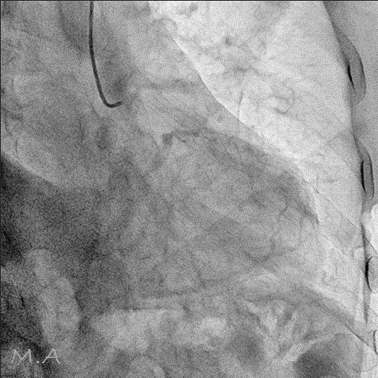

血管撮影装置

当院は令和6年3月の新病院発足に伴い、より高精度で安全な検査・血管内治療(IVR:Interventional Radiology)を提供するため最新の島津製作所製バイプレーンシステムTrinias B12s(Opera smart)を導入しました。

平面型X線検出器(FPD:Flat Panel Detector)を搭載し、カテーテルを用いた高度な血管内治療においてより少ないX線で高い解像度の画像を描出可能となりました。

バイプレーンシステムを採用したことにより、一回の造影剤注入で2方向撮影が可能となり、従来のシングルプレーンと比較して造影剤使用量を半分程度に抑えることができ、被ばくを低減すると共に検査時間の短縮にも繋がり、より患者さまの負担を軽減することが可能となりました。

冠動脈造影検査(CAG:Coronary Angiography)をはじめ、経皮的冠動脈インターベンション(PCI:Percutaneous Coronary Intervention)、下肢動脈のインターベンション(EVT:Endovascular Treatment)、肝動脈化学塞栓術(TACE:Transcatheter Arterial Chemo-Embolization)等、心血管領域、腹部血管領域における高度なカテーテル治療においてその性能を発揮しております。